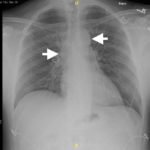

We present a case of a 51-year-old previously healthy man who presented to the ED complaining of chest pain that had resolved prior to arrival, and a mild headache. His vital signs were notable for hypotension, but physical exam was unremarkable. Chest x-ray revealed a borderline widened mediastinum. A standard ETTE was within normal limits, but additional SSNV demonstrated a dissection flap in the aortic arch. The patient was taken to the operating room for surgical repair 75 minutes after the ED ultrasound was performed; the operation was successful, and the patient was discharged to home post-operatively with good outcome.